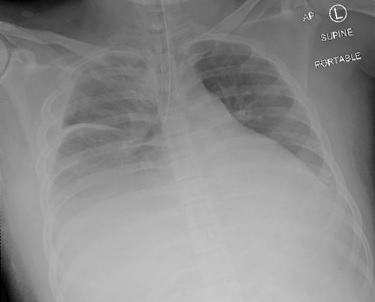

There was a concern for pulmonary compression from the enlarged liver herniation, creating difficulty in ventilation. The head of the bed was immediately raised to improve pulmonary compliance, and a significant improvement in ventilation with positive end-tidal CO2 was noted. Peak pressures at this time were noted to be elevated to approximately 35 cm H2O. Albuterol was administered through the endotracheal tube with slight improvement. The patient’s saturation improved to 100%. Bilateral breath sounds were noted on auscultation. Following the stabilization of the patient, we attempted to recline the head of the bed and noted significant difficulty in ventilation and elevation in peak airway pressures to ~50 cm H2O. An intraoperative chest X-ray was conducted to investigate the underlying cause. The X-ray showcased the endotracheal tube in the right bronchial mainstem ([Figure 3]). Subsequently, the patient was returned to a head-up position, and a fiberoptic bronchoscope was utilized to confirm the endotracheal tube placement 2 cm above the carina and patency of the airway. The patient’s oxygen saturation improved.